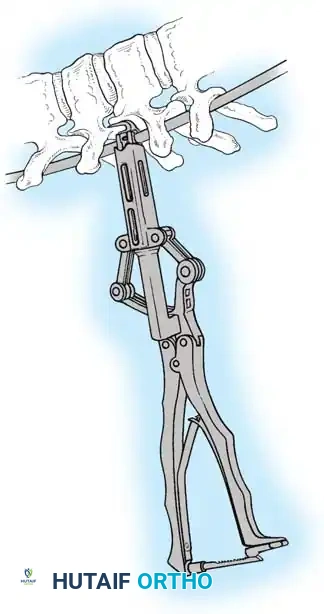

The Hall Technique

The Hall technique offers an alternative method for facet obliteration and grafting, particularly useful in rigid deformities.

Fig. 38-28: The Hall technique of facet fusion, involving sharp excision of the inferior facet and trough creation.

- Sharply amputate the inferior articular facet with a gouge and remove the bone fragment entirely. This exposes the cartilage of the superior facet.

- Remove the exposed cartilage completely with a sharp curet.

- Create a bleeding trough by removing the outer cortex of the superior facet.

- Impact cancellous bone grafts directly into this vascularized trough.

- Complete the procedure with global decortication of the posterior elements.